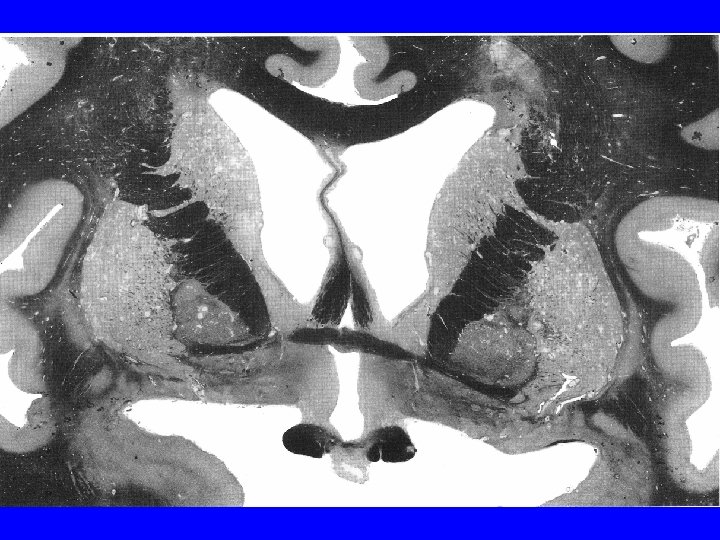

Clinical problems in basal ganglia • Huntington’s chorea – Progressive, untreatable, decreased function and dementia – Genetic defect in gene called huntingtin – Choreiform movements leading to severe impairment; death within 15 years – Loss of about 90% of striatal neurons, especially of indirect pathway: overactivity of direct pathway: uncontrolled movements

Normal Huntington’s Chorea